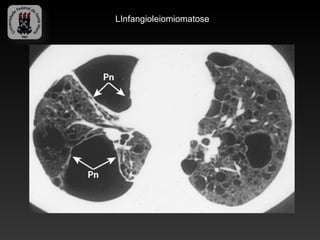

-LINFANGIOLEIMIOMATOSE

-Doença rara de etiologia incerta, caracterizada pela proliferação

desordenada de células musculares lisas.

-Afeta exclusivamente mulheres em idade reprodutiva.

-Achados:

-Finas apacidades reticulonodulares bilaterais (precoce)

-Hiperinsuflasão, faveolamento, reticulados grosseiros, derrames pleurais

quilosos e pneumotorax.

-TC: incontáveis cistos, com paredes finas e espalhados uniformemente.

-Parenquima pulmonar relativamente normal.

LInfangioleiomiomatose